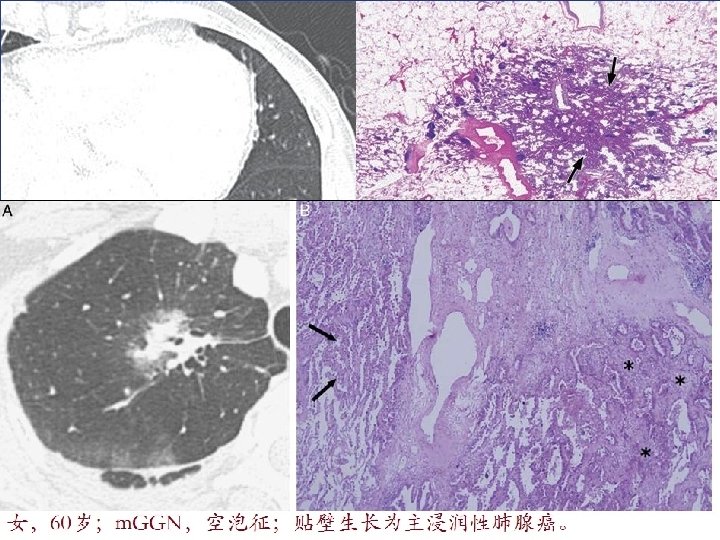

原位腺癌(AIS) LUNG NODULE v 原位腺癌(AIS)多为非粘液性,HRCT上表现为: • p. GGN,密度较AAH略高; • 直径一般> 5 mm; • 少部分AIS因肺泡壁塌陷而呈m.

原位腺癌(AIS) LUNG NODULE v 原位腺癌(AIS)多为非粘液性,HRCT上表现为: • p. GGN,密度较AAH略高; • 直径一般> 5 mm; • 少部分AIS因肺泡壁塌陷而呈m. GGN。 v AIS的预后:很好,手术切除后5年生存率达 100%。 Lee HY, et al. Am J Roentgenol 2014; 202: W 224 -33. Myrna CB, et al. J Thorac Imaging 2012; 27: 240 -6. Travis WD, et al. J Thorac Oncol 2011; 6: 244 -85. Yang ZG, et al. Am J Roentgenol 2001; 175: 1399 -1407. 四川大学华西医院 22